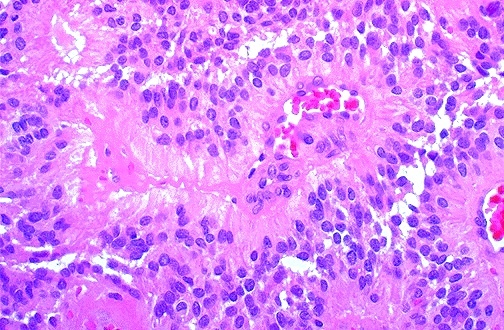

Oligodendroglioma

fried egg, calcifications, anastomosing capillaries, no mitotic activity, well circumscribed

Solid sheets with finely granular nuclear chromatin, surrounded by a halo of vacuolated cytoplasm